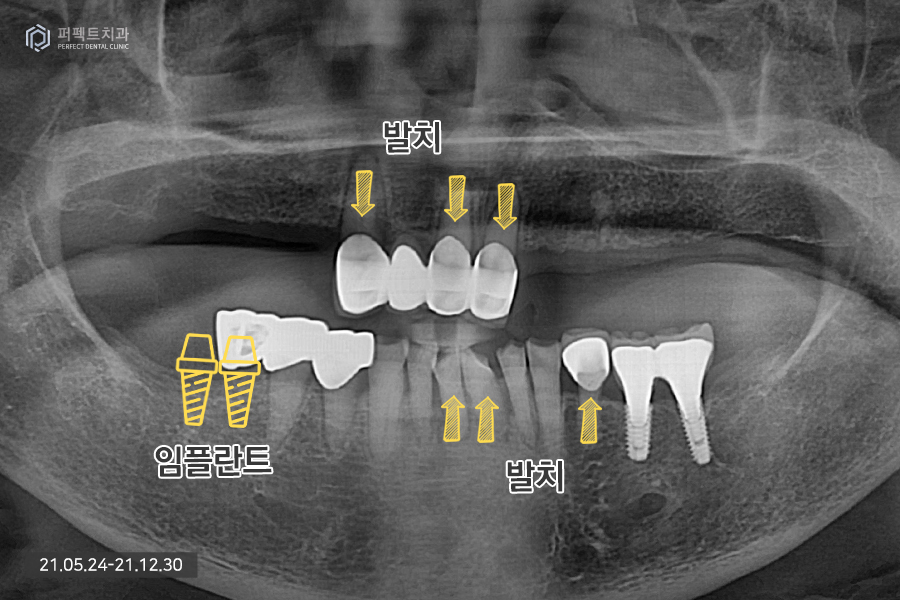

남아있는 앞니의 경우 3개가 남아있고 하나는 걸어서 사용하고 있는 상황이었는데 앞니가 심하게 흔들리고 있는 상황이라 모두 발치 하기로 결정을 하였습니다. 이런 경우 윗니는 치아가 하나도 없는 상태가 되어 전체 임플란트로 수복하게 됩니다.

아래 치아의 경우 멀쩡한 것처럼 보이지만 실제로는 그렇지 않습니다. 발치를 해야하는 치아들도 있고 치아가 없는 부분은 임플란트로 수복하기로 하였습니다.

윗니의 경우 치아가 전혀 없기 때문에 9개의 임플란트를 식립하였는데 이처럼 많은 양의 임플란트를 식립하는 경우 상황에 맞게 진료를 하게 됩니다.

일반적으로 위, 아래 14개의 치아, 총 28개의 치아가 있는데 전체 치아를 완성하기 위해서 최소 6개의 임플란트를 식립해야 하며 많은 경우 10개 혹은 그 이상의 임플란트를 식립하기도 합니다.

위 환자분의 경우 뼈가 굉장히 약한 뼈이기도 하고 골다공증도 있으셔서 심을 수 있는 곳에 가능한 많은 임플란트를 식립하기로 하였습니다. 완성된 사진을 보면 더 명확히 아실 수 있는데요.

그 이유는 첫번째, 임플란트 식립 환경이 좋지 않았기 때문입니다. 환자분은 골다공증도 있으셨고 뼈가 너무 물러서 임플란트를 식립할 수 없는 자리도 많이 있었기 때문입니다. 그러다보니 환자분께서는 임플란트를 식립할 수 있는 곳에는 임플란트를 식립하길 원하셨고 이로 인해 9개의 임플란트 식립, 5개의 치아를 걸어서 14개의 완성된 치아를 갖게 되었습니다.